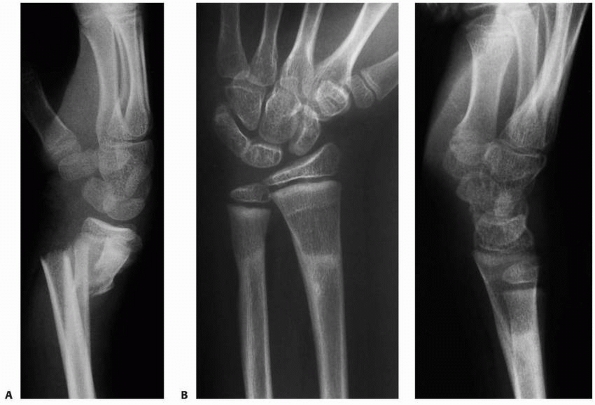

|

FIGURE 9-28 A.

AP radiogaph of distal radial growth arrest, ulnar overgrowth, and an ulnar styloid nonunion. Wrist arthroscopy revealed an intact triangular fibrocartilage complex. B. AP and lateral radiographs after ulnar shortening osteotomy. |